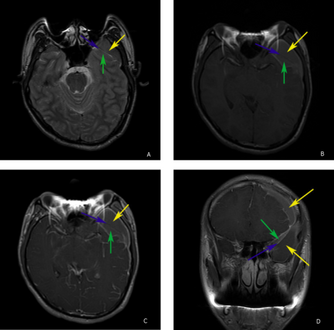

Arachnoid cyst.png

A CT scan of an arachnoid cyst

The diagnostic process typically begins with a medical history workup followed by a medical examination by a physician. Imaging tests, such as CT scans and MRIs, help provide a clearer picture. The physician typically looks for fluid (or other bodily substance) filled sacs to appear in the scans, as is shown in the CT scan of a colloid cyst. A primary health care provider will refer an individual to a neurologist or neurosurgeon for further examination. Other diagnostic methods include radiological examinations and macroscopic examinations. After a diagnosis has been made, immunohistochemistry may be used to differentiate between epithelial cysts and arachnoid cysts.[2] These examinations are useful to get a general idea of possible treatment options, but can be unsatisfactory to diagnose CNS cysts.[3][5] Professionals still do not fully understand how cysts form; however, analyzing the walls of different cyst types, using electron microscopes and light microscopes, has proven to be the best diagnostic tool. This has led to more accurate cyst classification and correct course of action for treatments that are cyst specific. In the past, before imaging scans or tests were available, medical professionals could only diagnose cysts via exploratory surgery.[2]